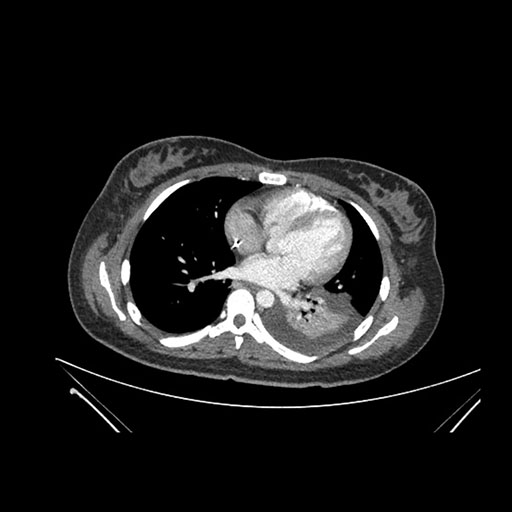

Imaging Analysis

Look through the patient's CT scan to identify any areas of concern for the necessary procedure.

Axial Venous

Based on initial findings, which issue(s) would you be most concerned about?